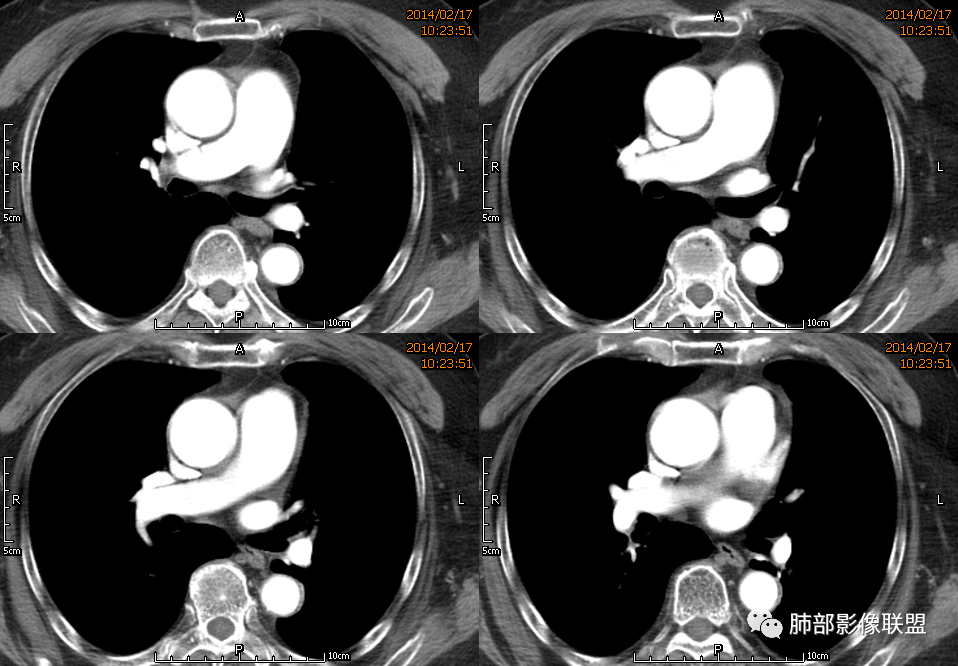

薏米: 老年女性,急性起病,咳嗽,咳痰,咯血,白细胞低,胸部CT提示左肺上叶可见一团块样密度增高影,边缘平直,部分略有膨隆,内可见支气管进入后截断,小的空洞,血管造影,坏死,明显强化,周边可见少许索条,考虑炎性病变,肺脓肿可能。鉴别结核,隐球菌。

一切∮随缘: 定位:肺内,左肺上叶肿块,呈长条状,平行血管束生长,边缘分叶,平扫密度均匀,增强后不均匀强化,可见低密度坏死,近段支气管及血管穿行病灶内,远端堵塞支气管,血管似有破坏,周围散在点状小结节,及纤维索条影,考虑恶性:腺癌,类癌,淋巴瘤。鉴别结核及隐球菌。

红星: 老年女性,咳嗽咳痰10天,痰中带血4天。左肺上叶前段胸膜下肿块影,沿支气管方向走行以膨胀生长为主,局部有收缩改变,支气管血管绝断,中间有小片状的坏死及小的空洞影,增强扫描病灶明显的强化,病灶周围网格状的小叶间隔增厚。拟左肺上叶前段浸润型腺癌并癌性淋巴管炎。鉴别诊断结核肉芽肿。

秦化君: 左肺上叶前段胸膜下软组织密度肿块影,边缘清晰,部分边缘膨隆,纵隔缘弧形内凹,脂肪界面清晰。肿块中心密度减低,支气管进入病灶后截断,似有扩张表现,病灶周围可见小叶间隔增厚,斑片影,近端支气管似管壁增厚。增强后明显强化,中心见低密度区。考虑:1.肉芽肿性炎?2.IMT?3.淋巴瘤?

傅昌瑜: 老年女性,咳嗽咳痰10天,痰中带血4天。左肺上叶前段胸膜下肿块影,沿支气管方向走行,膨胀生长为主,局部边缘似有收缩改变,中间有小片状的坏死,支气管进入,增强扫描病灶明显的强化,血管走形较自然(血管漂浮征?),病灶周围网格状的小叶间隔增厚。考虑淋巴瘤可能性大,注意鉴别炎性肉芽肿及肺腺癌。

水晶石头: 患者老年女性,咳嗽咳痰10天,痰中带血4天余。查血常规白细胞低;肿瘤标志物、凝血功能正常;血生化:蛋白低;C反应蛋白、血沉稍升高。胸部CT:左肺上叶前段胸膜下沿气管支气管走形肿块影,长轴与胸膜平行,见分叶、毛刺、支气管截断、空泡征象。增强明显强化,且见血管造影征及病灶内小灶低密度坏死区。左肺上叶尖后段见一结节灶。综合考虑恶性病变可能大,腺癌或淋巴瘤可能。鉴别诊断肺脓肿。

尘缘: 老年女性,咳嗽咳痰10天,痰中带血4天,白细胞及中性粒明显减低,轻度贫血。影像表现:左上叶肿块,边缘膨隆,局部平直,支气管稍扩张,进入后远端堵塞,内见小空洞及不规则坏死区,增强后强化明显,坏死边界较清,并见环状强化区,内部血管走行自然,周围见小叶间隔增厚呈大网格征。初步诊断:慢性炎性伴脓肿形成及肉芽组织增生。鉴别淋巴瘤及腺癌,先抗炎治疗后复查或直接穿刺明确。

张延军: 左肺上叶前段软组织影,偏下缘见充气支气管,部分支气管壁与肿块近端增厚狭窄。实性部分见血管穿行,边缘平直并局限性凹陷,增强扫描内见斑片状低密度区,界不清,实性部分中度强化,病变外宽内窄,基底贴于胸壁,周围肺组织内见条片状密度增高影,考虑炎性,结核?腺癌待排。

毛勤香: 老年女性,左肺上叶胸膜下肿块,部分膨隆部分收缩,边缘毛糙模糊,周围少许索片状影,小叶间隔增粗,支气管进入后截断,增强扫描明显不均匀强化,内低密度区无明显强化,血管走行尚可,首先考虑感染性变并脓肿形成,鉴别淋巴瘤,建议抗炎后复查。

3.病灶密度不均,中央坏死液化并见气泡影,支气管及血管贴边进入,较均匀环形强化(显示多层结构),未见明确壁结节。